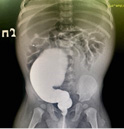

69-76 90

Аннотация

Актуальность. Тромбоэмболия легочной артерии (ТЭЛА) характеризуется острой перестройкой параметров центральной гемодинамики в большом и малом кругах кровообращения и является одним из частых жизнеугрожающих состояний среди взрослых пациентов. Несмотря на то что первое описание ТЭЛА было представлено фон Лешнером в 1861 году, до настоящего времени в педиатрической практике нет должной настороженности к подобному осложнению. Это объясняется не только отсутствием системных знаний о распространенности ТЭЛА в детской популяции, но и из-за стертости, а порой и нетипичной, в отличие от взрослого пациента, клинической картины. Неверная интерпретация имеющихся симптомов, ошибочная трактовка данных инструментальных методов исследования неизбежно приводят к неверному диагнозу: пневмония, сердечная недостаточность, дебют онкологического заболевания, что объясняет высокую летальность при ТЭЛА у детей.

Цель. Демонстрация случаев ТЭЛА при наличии значимых факторов риска — прием пероральных контрацептивов, снижение уровня протеинов C и S у двух девочек-подростков.

Материалы и методы. Представлены 2 случая клинически и/или инструментально подтвержденных эпизодов ТЭЛА у девушек 17 и 14 лет. ИМТ в одном и другом случае составил 25,9 и 25,15 кг/м2 соответственно. Среди инструментальных методов исследования были выполнены ЭКГ, трансторакальная ЭхоКГ, мультиспиральная компьютерная томография (МСКТ) с контрастированием. Лабораторная диагностика антифосфолипидного синдрома, анализ на тромбофилию были обязательным дополнением клиническому, биохимическому анализам крови и коагулограмме с определением уровня АТ-III и D-димера.

Результаты. Среди клинических симптомов, имеющих диагностическую ценность в дебюте заболевания, были одышка, боли в области грудной клетки, кашель, кровохарканье. Ни в одном, ни в другом случае эпизод ТЭЛА не привел к повышению давления в легочной артерии, о чем свидетельствовали показатели давления в правом желудочке (ПЖ): 24 и 20 мм рт. ст. соответственно. МСКТ с контрастированием подтвердила диагноз субмассивной ТЭЛА и признаки инфаркт-пневмонии в одном и другом случаях. УЗДГ не обнаружила источника ТЭЛА в сосудах нижних конечностей и малого таза ни у одной из девушек. Прием пероральных контрацептивов в одном случае и снижение уровня протеинов С и S в другом явились значимыми факторами развития ТЭЛА. Лечебная тактика заключалась в назначении низкомолекулярных гепаринов (НМГ) с переходом на непрямые антикоагулянты: апиксабан и варфарин соответственно. Выполненная через месяц МСКТ свидетельствовала о положительной динамике заболевания, но не полном восстановлении воздушности легочной ткани. Терапия непрямыми антикоагулянтами была продолжена.

Заключение. Частота встречаемости ТЭЛА в детской популяции реже, чем у взрослых, но это не снижает уровня значимости данного грозного осложнения в педиатрической практике. Центральные венозные катетеры, септические осложнения, длительная иммобилизация, шунтированная гидроцефалия, онкология, ожирение являются наиболее вероятными причинами ТЭЛА у детей, как и у взрослых пациентов. Прием оральных контрацептивов и наследственные тромбофилии в двух наших наблюдениях свидетельствуют о других не менее очевидных причинах возникновения ТЭЛА у детей подросткового возраста.